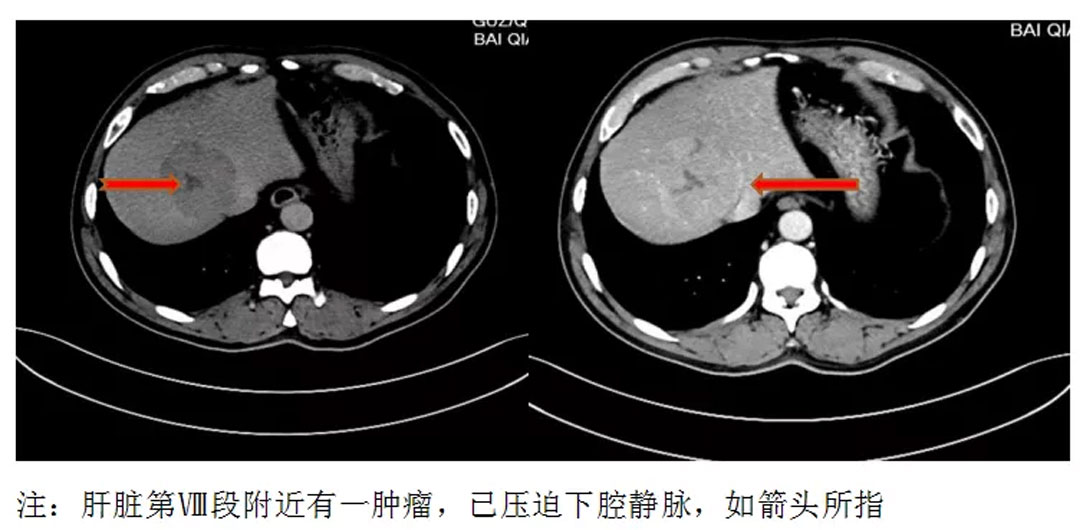

【友谊肝胆】妙手医生精准打击,完美切除巨块型肝癌_肝脏_王先生_肿瘤

图片尺寸829x616